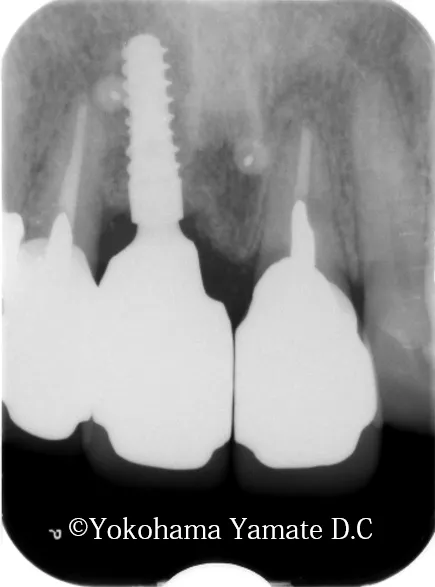

治療後(2022年11月20日)

新たに歯肉と骨を得て、歯周組織の復活と安定が得られて来ています。

抜歯後 20か月、インプラント埋入・GBR後 19か月、CTG後 15か月

上の顎の前歯のインプラント付近。aは骨が再生されたところ

歯肉の厚み3.62mm 骨の厚み3.55mmとなり凸して再生している

治療後には歯肉の厚みが3.5mm増加し、骨の厚みは1.63mm増加しました。それによって、このインプラントはより長くお口の中で機能していくことでしょう。